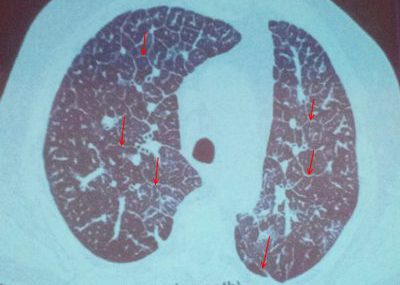

Правильной постановке диагноза помогают своевременно проведенные диагностические исследования. Определить наличие булл и точно поставить диагноз помогают следующие методы диагностики:

1. Осмотр пациента и сбор анамнеза (наличие или отсутствие хронических заболеваний пациента, экологическую обстановку в месте его проживания, приверженность к курению).

2. Метод перкуссии помогает определить участок повышенной воздушности.

3. С помощью аускультации выявляют сухие свистящие хрипы.

4. Томография и рентгенография.

5. Анализ крови направлен на процентное определение углекислого газа и кислорода.

6. Спирометрия помогает просчитать дыхательные объемы.